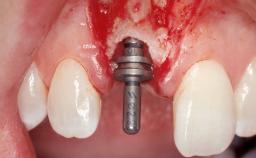

Immediate Placement of an Implant in a Maxillary Left Central Incisor Site

A 33-year-old female patient presented with an upper left central incisor that required extraction after a failed endodontic therapy. The tooth had been traumatized when the patient was a teenager and had undergone several endodontic treatments, including two apicectomy procedures. The patient was in good health and did not smoke. Clinical examination showed that the patient had a high lip line. In full smile, the gingival margins of the upper teeth were visible to the first molars. The gingival margins of central incisors 11 and 21 were only just showing. Examination of tooth 21 confirmed that the tooth was mobile and had hypererupted by 1 mm.

Type of Implants One-Piece

Bone Augmentation Horizontal|Simultaneous

Augmentation Materials Xenogenous|Membrane

Soft Tissue Grafting Simultaneous

Placement Protocol Immediate implant placement